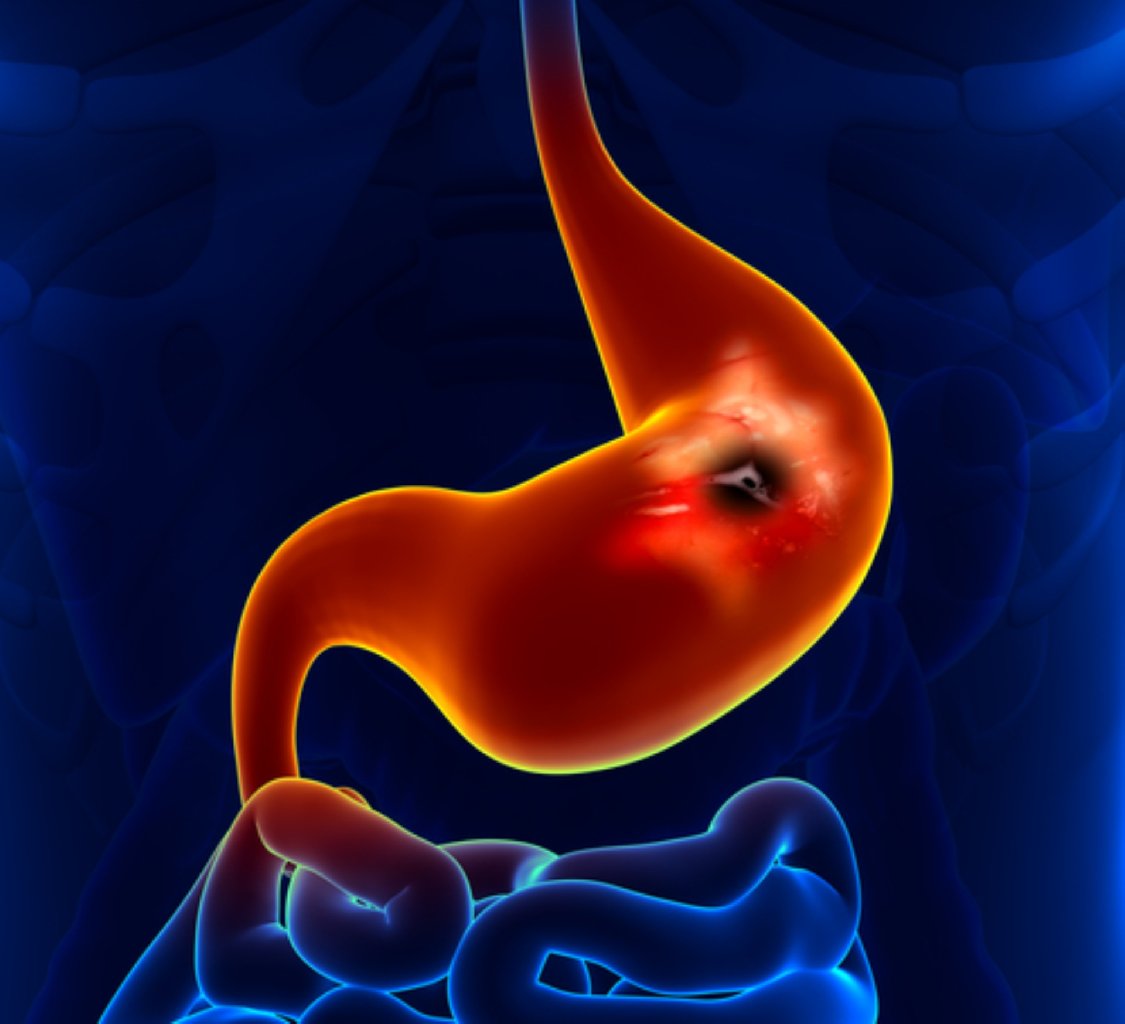

Mide ülserinin ən tipik simptomu, qarnın üst hissəsində, mədə bölgəsində meydana gələn kəskin və yan ...

Risk Faktorları: Helikobakter Pilori İnfeksiyası: Mədə ülserlərinə səbəb olan bu bakteriya, mə ...